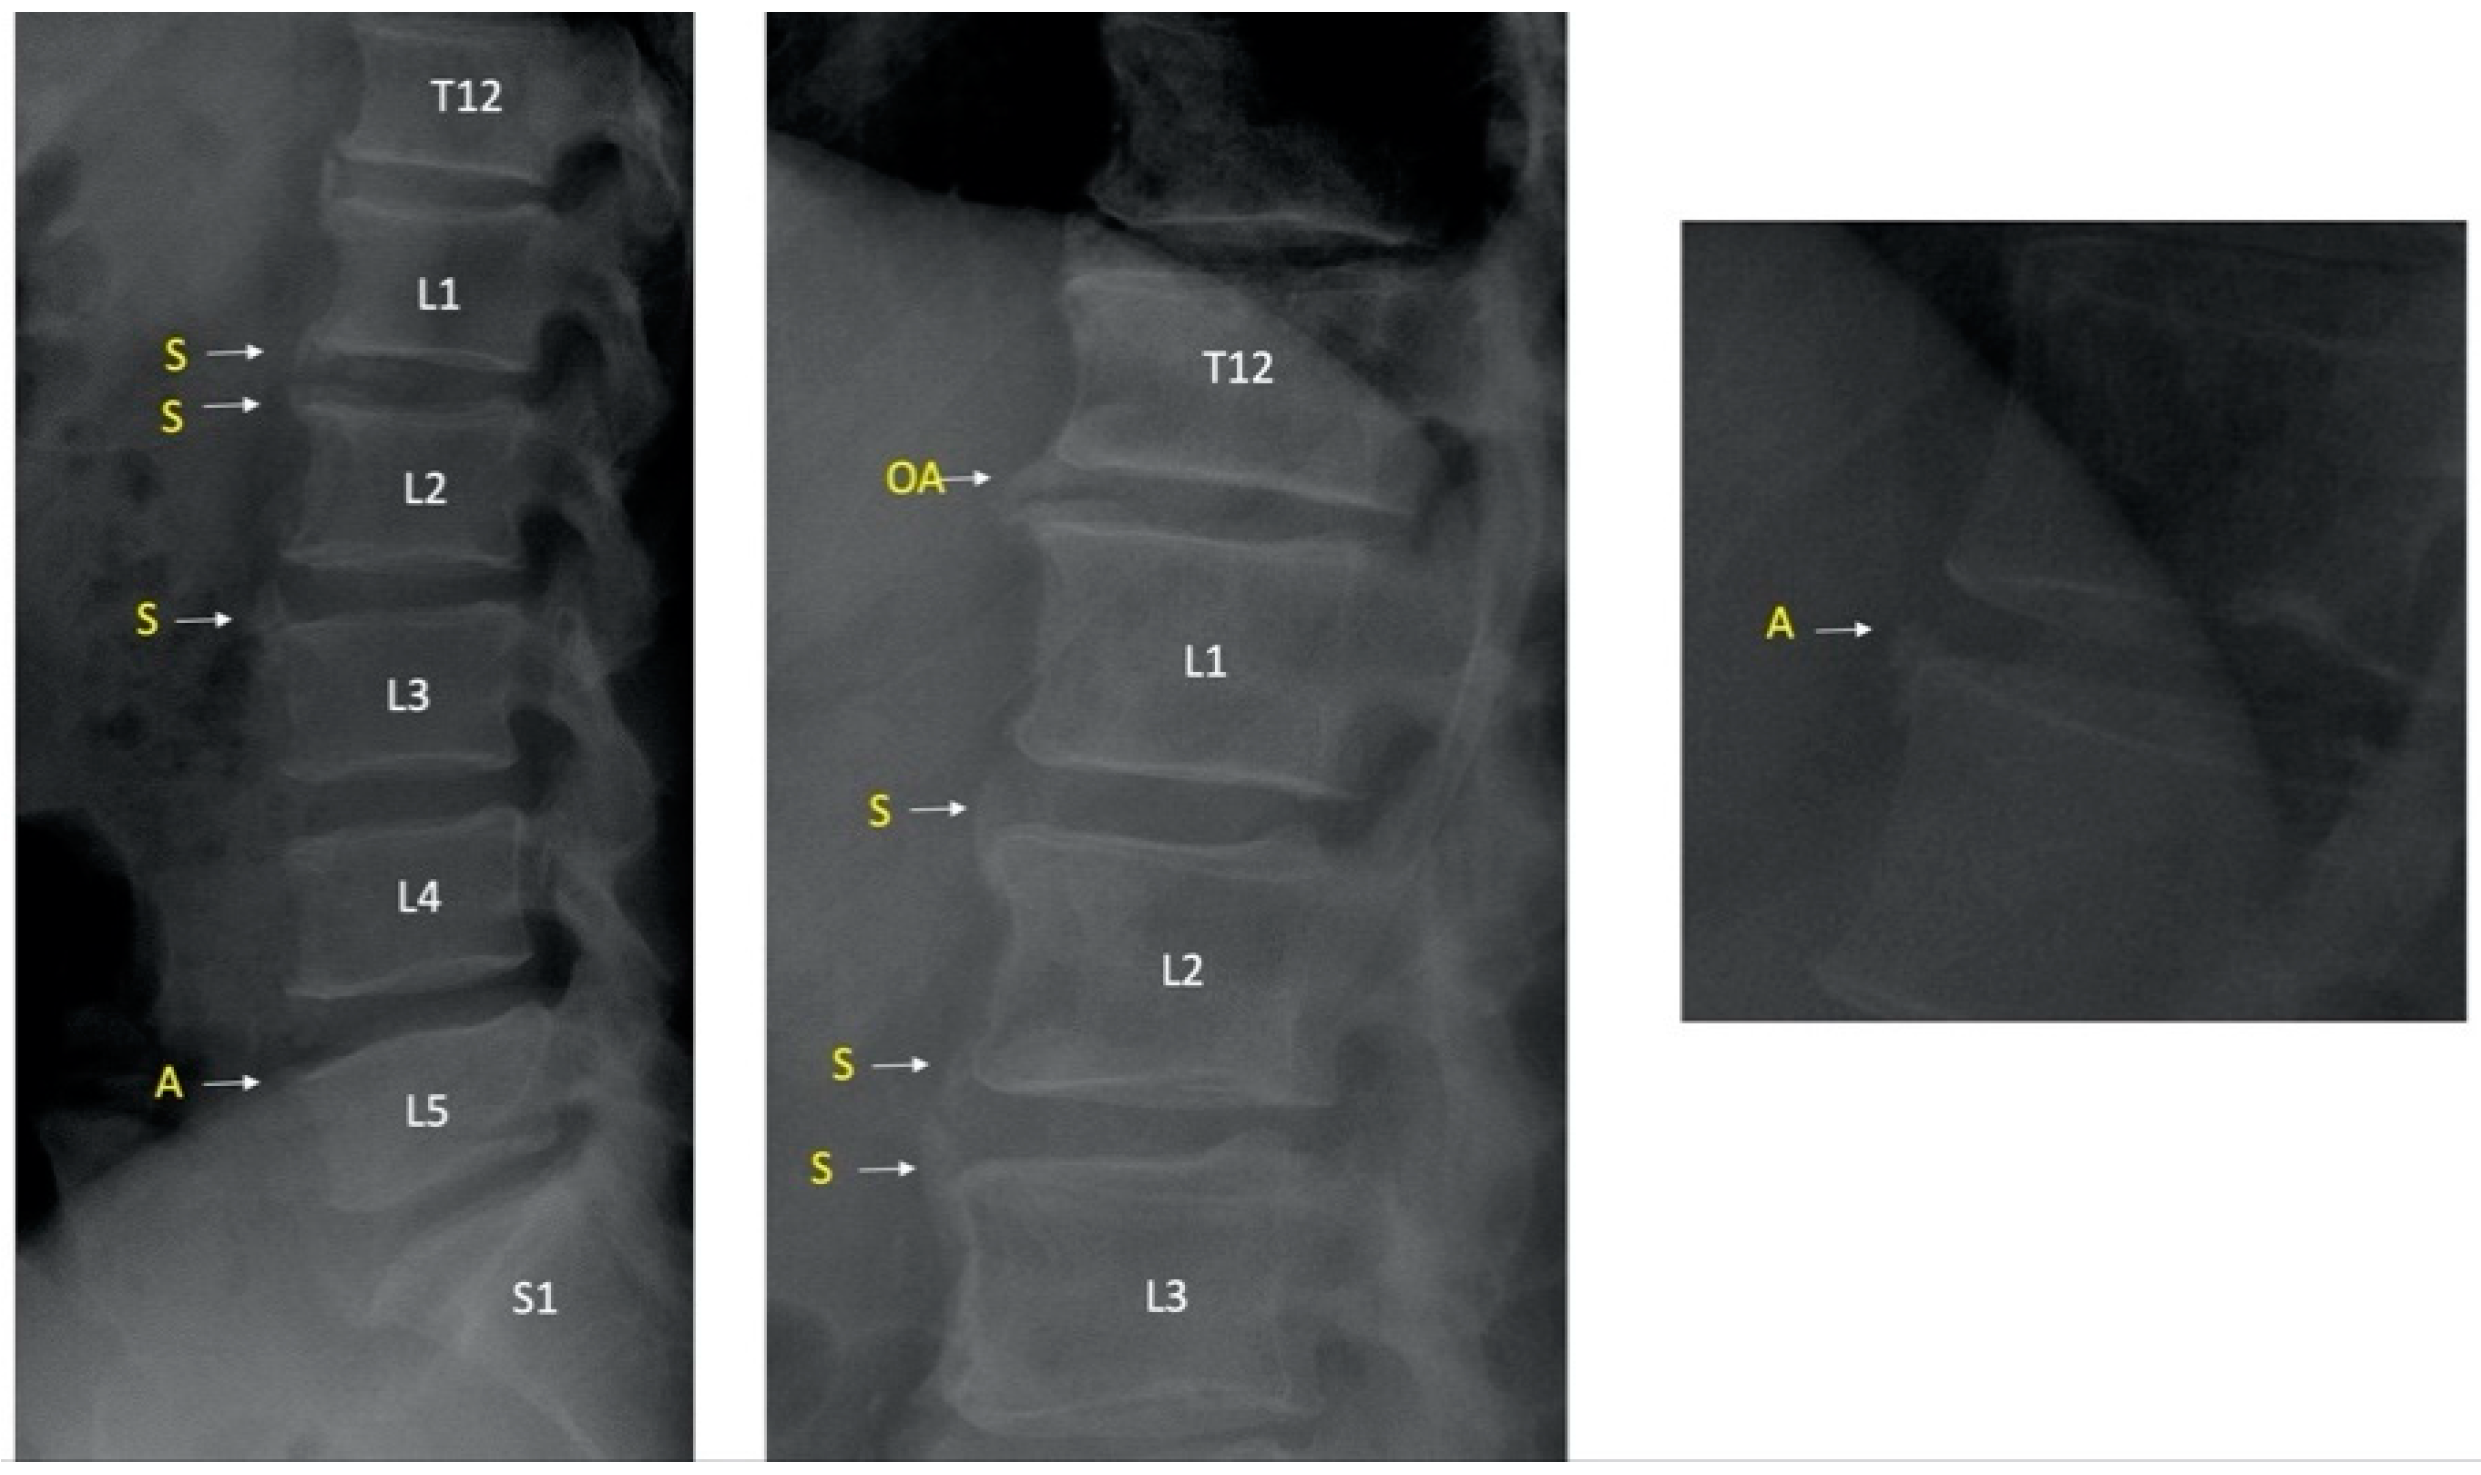

2.4. Pelvic and Lumbar X-ray Readings and Definitions

3.5. Ambiguous Lesions on Lateral Lumbar Radiograph in PsA Patients